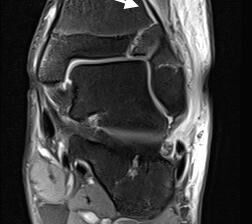

MRT

Die Kernspintomographie hat ihre Stärke in der Darstellung von Weichteilverletzungen. Insbesondere Verletzungen der Wachstumsfuge, des Periosts und der Bänder lassen sich gut visualisieren. Nachteilig ist die Untersuchungsdauer von 20-30 Minuten. Bleibt das Kind während dieser Zeit nicht ruhig liegen, kommt es zu Bewegungsartefakten, welche die Beurteilbarkeit der Bilder beeinträchtigen.

Fugengelenkfrakturen treten typischerweise vor dem 10. Lebensjahr auf, in einer Phase, in welcher die Wachstumsfugen noch weit offen sind. Dieser Frakturtyp betrifft fast ausschließlich den medialen Malleolus. Laterale Frakturen sind extrem selten, teilweise kommt es zu lateralen Bandverletzungen oder Fugenschaftfrakturen der distalen Fibula. Die Frakturlinie verläuft in einer Verlängerungslinie von der medialen Taluskante nach proximal. Häufig stellen sich Verletzungen des Innenknöchels im Röntgenbild schlechter dar, insbesondere wenn die Aufnahmen verdreht sind oder die Ebene der Fraktur bei geringer Dislokation verkippt zur Röntgenebene liegt. Besteht klinisch der geringste Hinweis auf eine Verletzung des Innenknöchels, muss aufgrund der Tragweite der Verletzung durch entsprechende Aufnahmen gegebenenfalls auch Schnittbildverfahren die Verletzung sicher diagnostiziert oder ausgeschlossen werden (Abb. 15).

Osteochondrale Verletzungen können infolge eines Distorsionstraumas beobachtet werden (Taluskantenfraktur), teilweise lässt sich auch kein Trauma eruieren. Der es sich bei osteochondralen Verletzungen um keine Arthrose handelt, ist gerade bei Schmerzfreiheit ein defensives Vorgehen angezeigt. Bei offenen Wachstumsfugen kann eine osteochondrale Verletzung unter konservativer Therapie ausheilen.

Eine retrograde Anbohrung ist indiziert, wenn sich im MRT Verlauf eine zunehmende Sklerosierung im Randbereich der Läsion zeigt bei intakter Knorpeloberfläche.

Instabile Knorpelareale werden arthroskopisch entfernt in Verbindung mit einer Mikrofrakturierung der subchondralen Knochenlamelle.